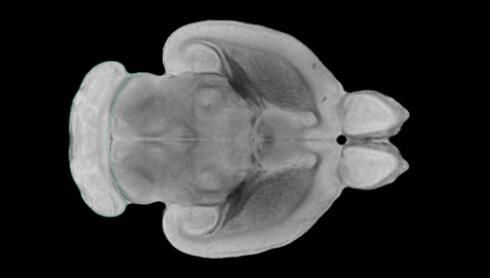

近日,一項刊登在國際雜志Nature上的研究報告中,來自劍橋大學(xué)的科學(xué)家們通過研究揭示了隨著年齡增長大腦僵硬程度的增加導(dǎo)致大腦干細(xì)胞功能異常的分子機制,同時研究者還開發(fā)出了一種新方法能將老化的干細(xì)胞逆轉(zhuǎn)回年齡健康狀態(tài);相關(guān)研究結(jié)果有望幫助研究人員理解機體大腦的老化過程以及如何開發(fā)治療年齡相關(guān)大腦疾病的新型療法。

隨著機體年齡增加,肌肉和關(guān)節(jié)都會變得僵硬,這就會使得日?;顒幼兊酶永щy,本文研究表明,我們的大腦也是如此,與年齡相關(guān)的大腦僵硬對大腦干細(xì)胞的功能或許有著重要影響。文章中,研究人員對年輕和老化大鼠的大腦進行研究闡明了年齡相關(guān)大腦僵硬對少突膠質(zhì)前體細(xì)胞(OPCs,oligodendrocyte progenitor cells)功能的影響。OPCs是一類對維持正常大腦功能非常重要的大腦干細(xì)胞,其對于髓磷脂的再生也非常重要,髓磷脂是神經(jīng)組織周圍的脂肪鞘,在多發(fā)性硬化癥中髓磷脂的再生常常會被損傷,機體老化對這些細(xì)胞的影響常常會誘發(fā)多發(fā)性硬化癥的發(fā)生,這些細(xì)胞的功能在老化的健康人群中同樣會下降。

為了確定老化OPCs的功能缺失是否可以被逆轉(zhuǎn),研究人員將來自老化大鼠機體的老化OPCs轉(zhuǎn)移到了年輕大鼠柔軟的海綿狀大腦組織中去,值得注意的是,這些老化的大腦細(xì)胞能夠重新恢復(fù)活力,其行為非常像年輕更加強壯的細(xì)胞。這項研究中,研究人員在實驗室中開發(fā)出了具有可變僵硬程度的新型材料,并在受控環(huán)境下研究這些材料的生長及其對大鼠大腦干細(xì)胞的影響,這些材料能被工程化改造具有和年齡或老化大腦相似的柔軟程度。